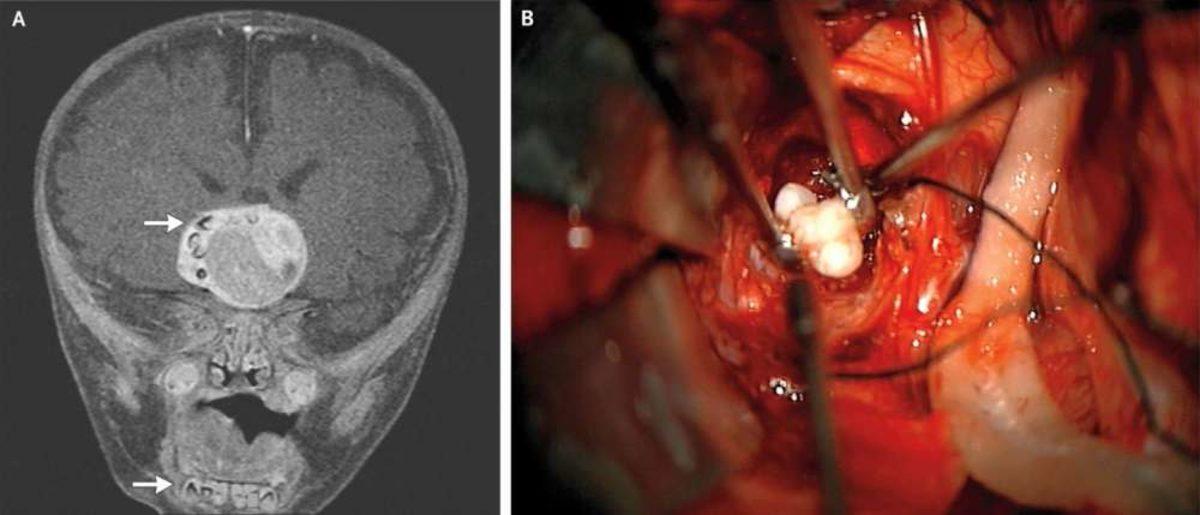

2014 yılında yaşanan vakada, Maryland Üniversitesi ve Johns Hopkins Çocuk Merkezi’nden nörocerrahlar, 4 aylık bir bebeği MRI beyin taramasından geçirdi.

Tarama işlemleri sonucunda çocuğun beyninde ceviz büyüklüğünde bir tümör keşfetti. Tümörün sağ tarafında ise çok sayıda küçük çıkıntı göze çarpıyordu. Bebeği hızla ameliyata alan cerrahlar tümörü aldı. Büyüyen kısmın craniopharyngioma adı verilen, embriyotik dokunun dönüşümüyle ortaya çıkan bir beyin tümörü olduğu ortaya çıktı. Genelde beynin hormon salgılama merkezine yakın olan bu yapılar, vakaların çok büyük bir kısmında salih tümörler oluyor (yani kansere dönmeyen ve yayılmayan çeşit) ancak hormonal merkeze yaptıkları baskı nedeniyle sorun yaratabiliyorlar.

Ancak vaka ile ilgili ilginçlikler bununla sınırlı kalmadı. Cerrahlar, tümörde birkaç tane tamamen gelişmiş diş buldular. Teratoma olarak bilinen bu yapılar, genelde farklı doku türleri bulundurabiliyorlar. Bu dokular saç, kas, kemik gibi farklı türlerden olabiliyor. Yine de doktorlar neden bu tümör üzerinde diş oluştuğunu bilmiyor.